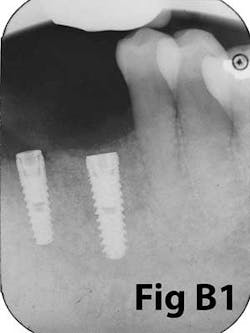

Fig. 6: Implants placed in lateral window sinus graft with no augmentation of attached tissue.